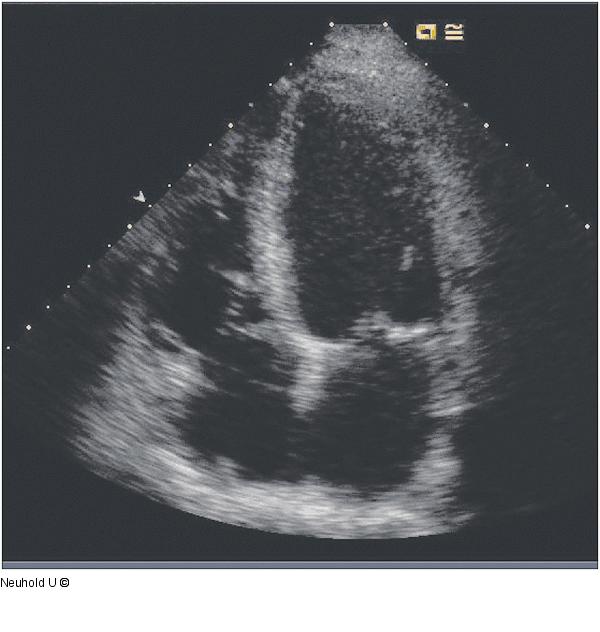

Abbildung 18: Vierkammerblick Vierkammerblick 4 Tage postoperativ |

Vierkammerblick 4 Tage postoperativ |